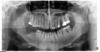

Luger Опубликовано 7 июля, 2013 Поделиться Опубликовано 7 июля, 2013 Почему лохмотья получаются?исходя из опыта,хотя может повлияло то что в настройках чаще в режиме турбо работаю. Как например тут.Кейс не идеальный,и очень бюджетный. Показываю в каких случаях использовал пьезо,и получал лохмотья. На сегодняшний день скрепил бы мини пластиной для остеосинтеза.И добавил графт+ мембраны ПТФЕ с усилением. Ссылка на комментарий

sergio Опубликовано 7 июля, 2013 Поделиться Опубликовано 7 июля, 2013 исходя из опыта,хотя может повлияло то что в настройках чаще в режиме турбо работаю. Как например тут.Кейс не идеальный,и очень бюджетный. Показываю в каких случаях использовал пьезо,и получал лохмотья. На сегодняшний день скрепил бы мини пластиной для остеосинтеза.И добавил графт+ мембраны ПТФЕ с усилением.при таком махровом генерализованном пародонтите мембраны ПТФЕ с усилением противопоказаны, имхо. да и пластина зачем, если есть 1,5 см базиса? Ссылка на комментарий

Luger Опубликовано 7 июля, 2013 Поделиться Опубликовано 7 июля, 2013 (изменено) при таком махровом генерализованном пародонтите мембраны ПТФЕ с усилением противопоказаны, имхо. да и пластина зачем, если есть 1,5 см базиса?Опять же из опыта,при генерализованном,работал в сегменте 34-37 (Как раз с птфе) после удаления зубов+кистогранулем поднял вертикально плюс по ширине с одномоментной имплантацией.Произошло оголение мембраны через 2 недели,после месяца вынул мембрану,было немного белого эксудата,графт не высыпался,вел на гиалуроне,до вторичного натяжения.все прижилось,естественно требуется работа с мягкими тканями. Вдаваться в подробности кейса не буду нечем подкрепить сказанное( отсутствие фото) пороюсь в архивах,если найду орто+к.т. выложу..По поводу пластины-предупреждение перелома.Род деятельности предполагает возможные лицевые травмы.Он был проинструктирован но тем не менее... К сожалению не все пациенты которым показана тотальная хирургическая санация,могут позволить себе несъёмное протезирование в дальнейшем.в лучшем случае проходят лечение сегментарно.. Это каждодневные реалии.. Изменено 7 июля, 2013 пользователем Luger 1 Ссылка на комментарий